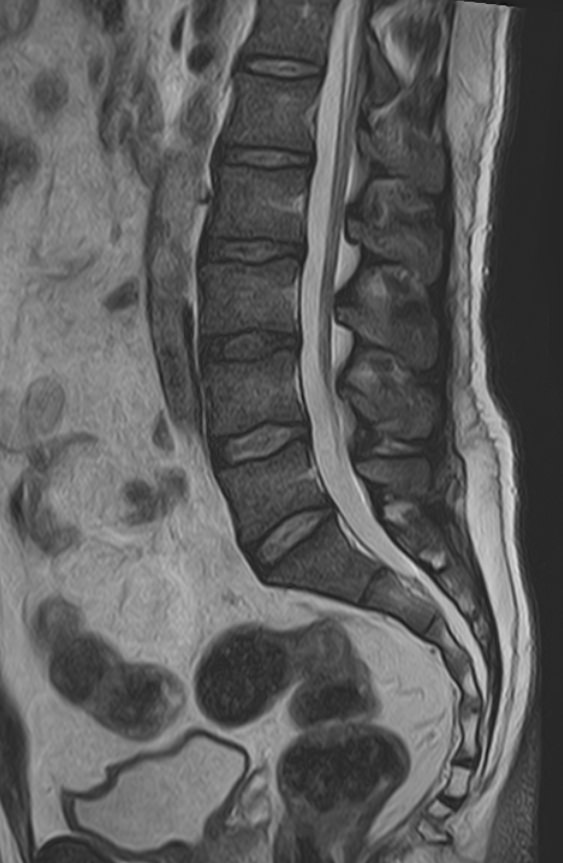

Магнитно-резонансная томография является наиболее чувствительным и эффективным методом диагностики различных заболеваний позвоночника. Метод позволяет оценить состояние костных структур позвонков, позвоночного канала с расположенным в нем спинным мозгом и окружающих мягких тканей, кроме того является основным способом диагностики демиелинизирующих заболеваний спинного мозга.

В клинике «Доступная медицина» установлен новейший высокопольный томограф экспертного класса TOSHIBA VANTAGE TITAN 1,5 Тесла, на котором выполняется комплексное обследование позвоночника. За счет высокой напряженности магнитного поля аппарат при сканировании создает изображения на плоскости превосходной четкости, затем с помощью компьютерных приложений данные преобразуются в изображения трехмерного формата, что обеспечивает точность и достоверность диагностики.

Что покажет МРТ всего позвоночника – 3 отдела + копчик

Данное комплексное обследование позволяет выявить следующие патологические состояния:

• Дегенеративные-дистрофические заболевания в шейном, грудном, пояснично-крестцовом отделах позвоночника и копчике (спондилез, спондилоартроз, остеохондроз).

• Грыжи межпозвонковых дисков (протрузии, экструзии).

• Стеноз (сужение) позвоночного канала.

• Патологические изгибы позвоночника, сколиоз, усиленный или выпрямленный лордоз как нарушение статической функции позвоночника.